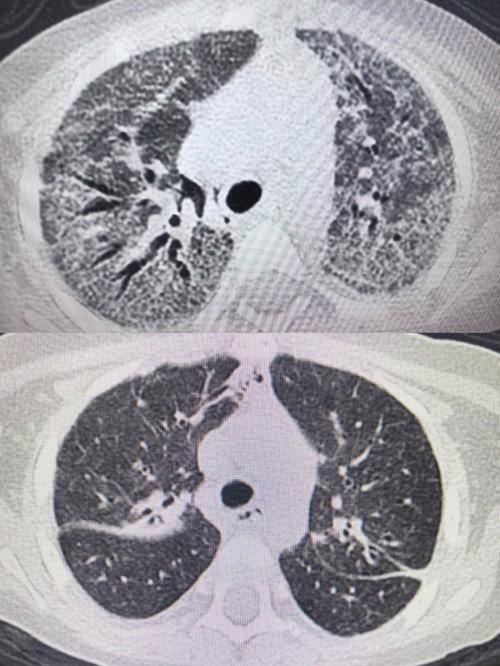

2025年12月10日,小佩因发热2天、气促半天被收治入院。该患儿一年前确诊急性淋巴细胞白血病,此次在维持化疗阶段发生肺部耶氏肺孢子菌感染,病情迅速进展为重度急性呼吸窘迫综合征并继发呼吸衰竭,后进一步发展为肺纤维化。入院时,小佩表现为呼吸急促、精神萎靡、尿量减少及经皮血氧饱和度持续下降,生命体征不稳。

PICU团队接诊后立即启动应急救治流程。在给予呼吸支持、抗感染治疗及纤维支气管镜检查与肺泡灌洗后,患儿氧合状态一度维持稳定。12月11日凌晨,其血氧饱和度再次下降,无创呼吸机辅助通气难以维持,医护团队果断行气管插管,转为有创呼吸机辅助通气。由于呼吸机参数持续处于高位,科室随即组织多学科专家会诊,制定并实施“个体化综合救治方案”,涵盖呼吸功能支持、肺康复治疗、抗感染管理、营养干预及皮肤与口腔护理等多个方面。针对肺部感染及纤维化,救治团队先后实施五次纤维支气管镜下肺泡灌洗术、三次间充质干细胞治疗及两次NK细胞治疗,并根据病情动态调整抗感染方案。在60天救治过程中,小佩的呼吸支持方式经历了从无创通气、气管插管、气管切开,最终降至鼻导管吸氧的逐步过渡,肺功能逐步恢复。